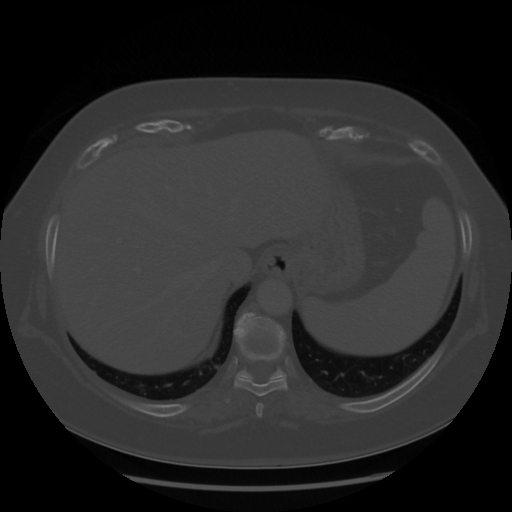

Original NATIVE CT scan (input)

Lung window (WL -600, WW 1500 β†’ Low βˆ’1350, High +150)

Mediastinum window (WL 40, WW 400 β†’ Low βˆ’160, High +240)